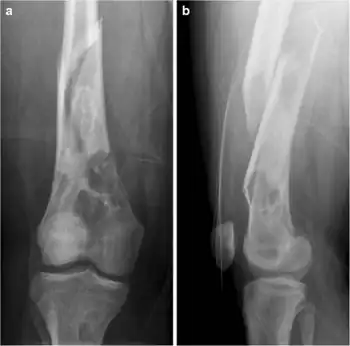

| Jaffe-Campanacci-Syndrome, boy 7 Y, tibial bowing and cortical/subcortial mixed sclerosis | |

Jaffe–Campanacci syndrome is one of the disorders associated with café au lait macules (CALMs). Presentations may include intellectual disability, disseminated non-ossifying fibromas of the long bones and jaw, hypogonadism or cryptorchidism, or giant cell granulomas of the jaw.[2]